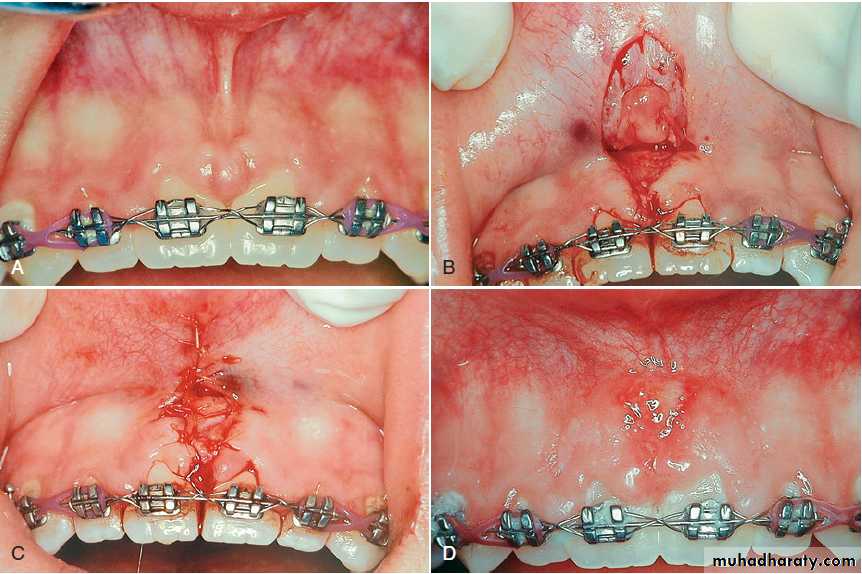

Frenectomy is complete removal of the frenum, including its attachment to underlying bone, and it may be required in the correction of an abnormal diastema between the maxillary central incisors.

Frenotomy is relocation of the frenum, usually in a more apical position.

Removal of the frenum. (A) Preoperative view of frenum between the two maxillary central incisors. (B) Removal of the frenum from the lip and gingiva. (C) The site is sutured after a connective tissue graft is placed over the wound. (D) Postoperative view at 2 weeks.